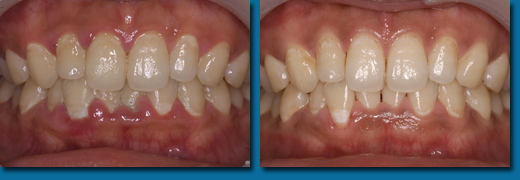

歯の磨き方が悪いと虫歯にもなりますが、磨き残した歯垢が唾液と反応して硬い歯石になって歯にこびり付いてしまいます。歯石になると歯ブラシでは取れなくなり、その中には沢山のバイ菌が潜んでいるために周りの歯肉が赤く腫れてしまいます。歯ブラシがあたると出血しやすくなりそのまま放置すると歯槽のう漏に進行していきます。歯石の除去を行い毎日の歯磨きをしっかり行うことで歯肉の状態はビックリするぐらい良くなります。歯石の除去は歯科衛生士の上手い下手が最も出る部分で、当院の歯科衛生士も歯石の取り残しがないように日々努力しています。左が歯石を取る前、右が取った後です。